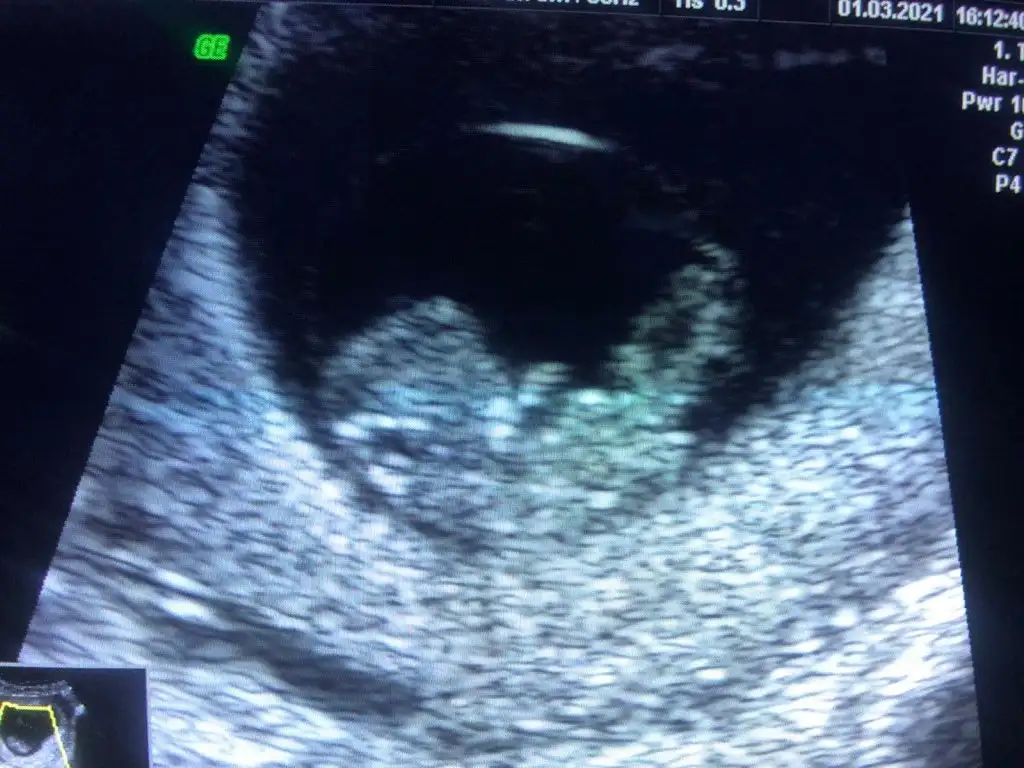

merhaba kızlar bu bebeğimin 9 haftalık karından ultrason resmî daha önce 6 haftalık halini atmıştım ramzi teorisi için erkek dediler hep başka profillerde de

merhaba kızlar bu bebeğimin 9 haftalık karından ultrason resmî daha önce 6 haftalık halini atmıştım ramzi teorisi için erkek dediler hep başka profillerde deama doktorum ramziye göre plasentanın yerine bakılır kız gbi dedi